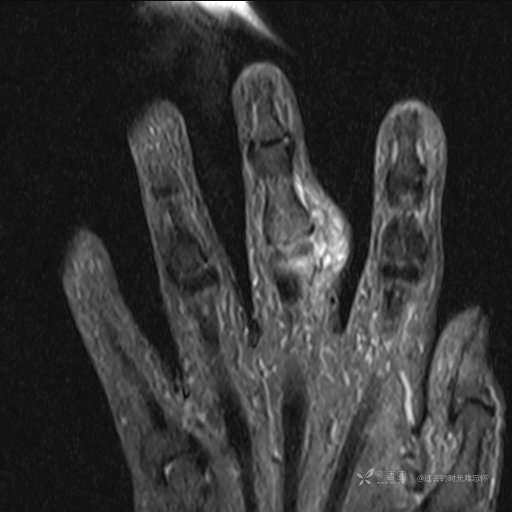

患者性别:女

患者年龄:59岁

主诉: 手指肿胀2年,其间明显肿胀,抗炎后肿胀减轻,近几日肿胀疼痛加重。

T1

提示:小指是伪影。